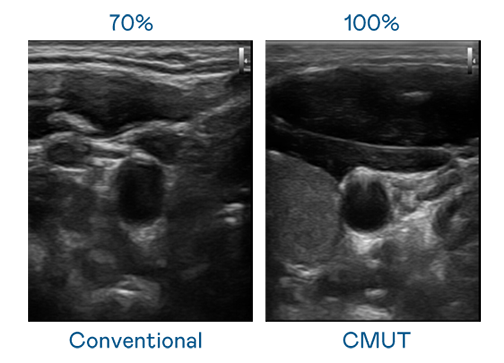

CMUT 技术是一种用电容式微机电元件来产生超音波讯号的技术。与传统 PZT 压电式技术相比,CMUT 频宽增加 30%,更宽频的超音波讯号让影像解析度大幅提升,是实现高影像品质医疗超音波扫描、促进精准医疗发展的关键技术。

超音波影像的解析度高低,首先取决于探头能发出的讯号频宽。太阳集团城娱8722 CMUT 可提供高清晰的超音波讯号,提供高频宽、高灵敏度、影像纹理细节更高的超音波影像,协助医护人员缩短影像判读时间及利用精准的医疗影像进行诊断。